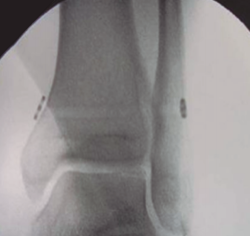

El método de tratamiento convencional suele ser la fijación de la sindesmosis con un tornillo de cortical a través del peroné situado a 2 o 3 cm por encima de la línea articular para evitar lesiones de los ligamentos y angulado de 20 a 30° anterior y medial(14,15). Se ha demostrado que 2 tornillos ofrecen mayor resistencia que un tornillo simple y que los tornillos de 4,5 mm son más resistentes que los de 3,5 mm. Más de 2 tornillos o de mayor diámetro no son aconsejables, ya que pueden provocar una fractura del peroné(2). Según lo publicado hasta ahora, no hay diferencias significativas entre el paso de 3 o 4 corticales. La carga completa no se recomienda hasta al menos 2 meses, una vez retirado el tornillo, para evitar roturas o síntomas dolorosos en la articulación del tobillo. Si bien está en discusión, ya que no parece haber diferencia significativa en el resultado funcional entre los pacientes que se sometieron a la extracción de rutina del tornillo transindesmal y los pacientes en los que el tornillo solo se extrajo en caso de implantes sintomáticos(16)(Figura 3).

Figura 3. Fijación rígida con tornillos.